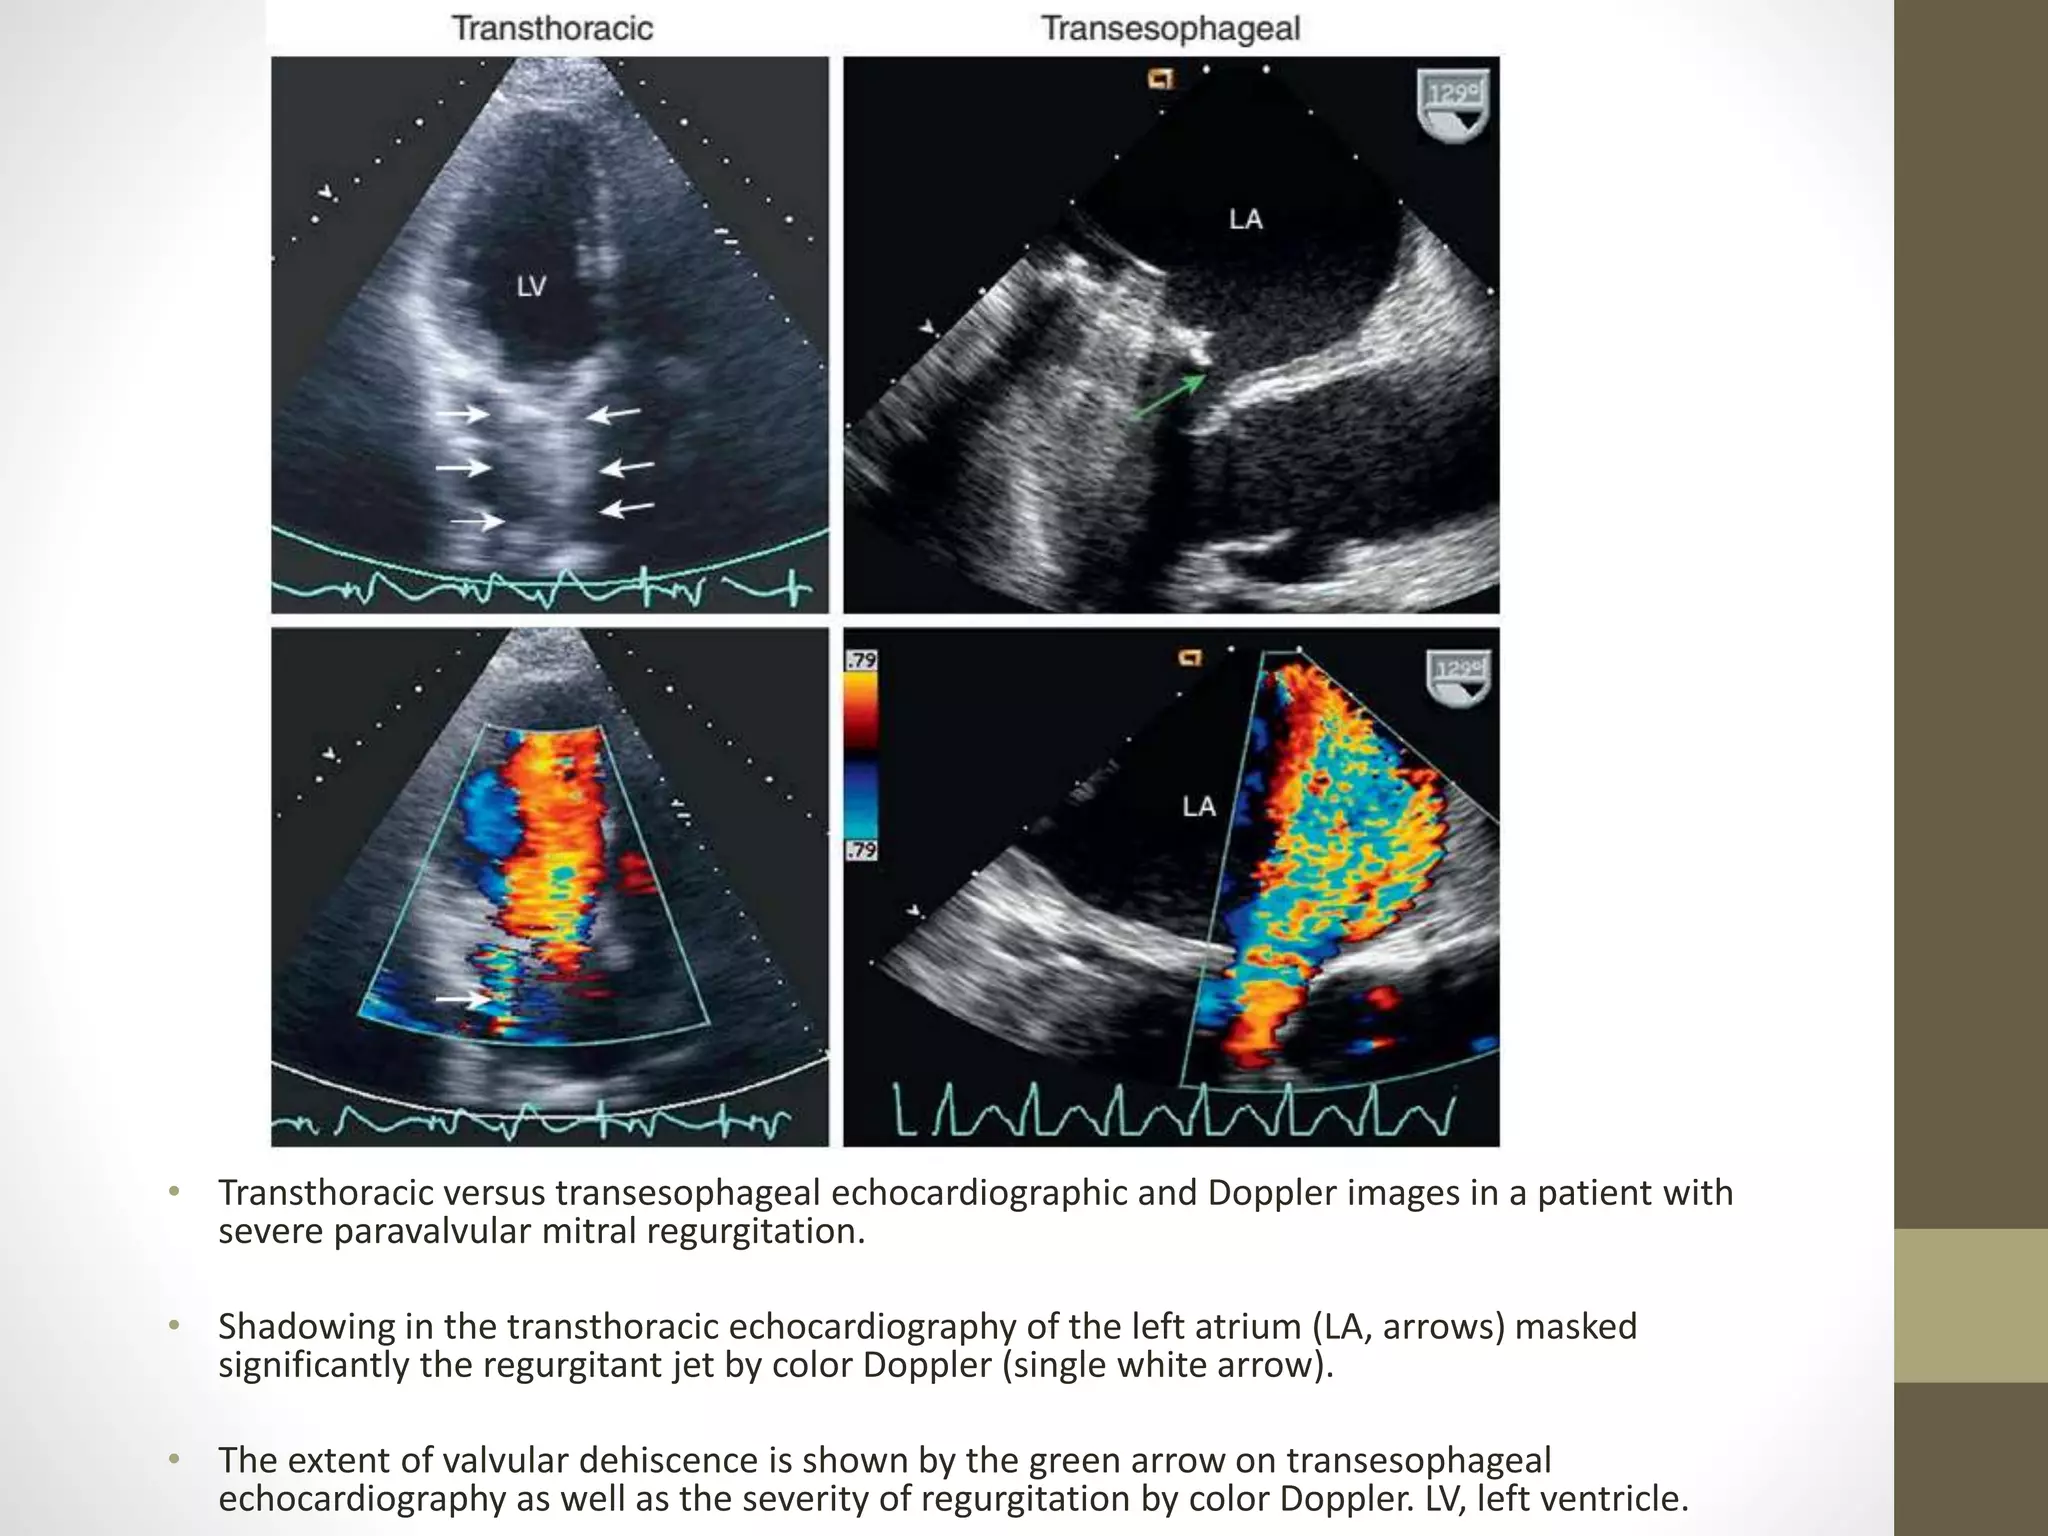

• Transthoracic versus transesophageal echocardiographic and Doppler images in a patient with

severe paravalvular mitral regurgitation.

• Shadowing in the transthoracic echocardiography of the left atrium (LA, arrows) masked

significantly the regurgitant jet by color Doppler (single white arrow).

• The extent of valvular dehiscence is shown by the green arrow on transesophageal

echocardiography as well as the severity of regurgitation by color Doppler. LV, left ventricle.